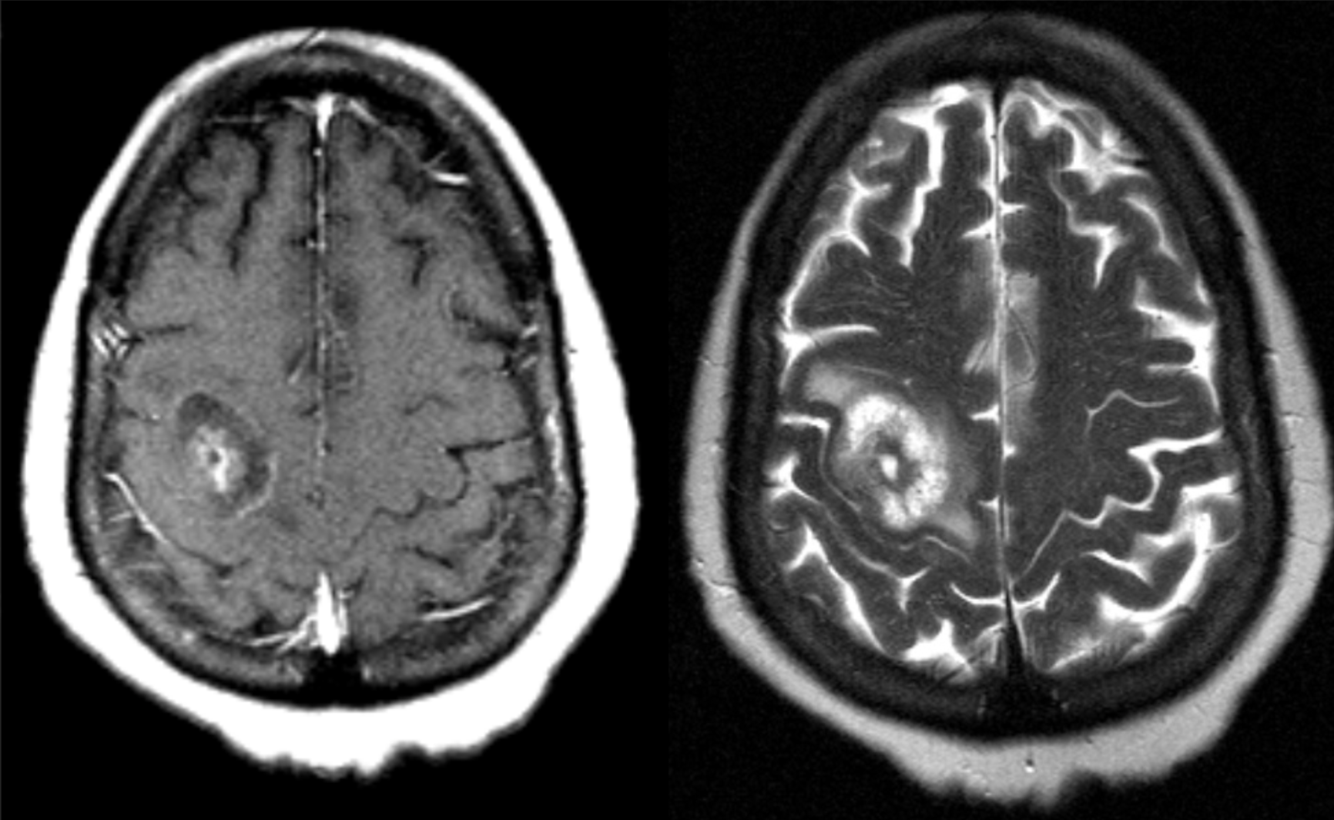

A 54 year-old man presented with headaches and weakness on his left side.

Abscess

Imaging